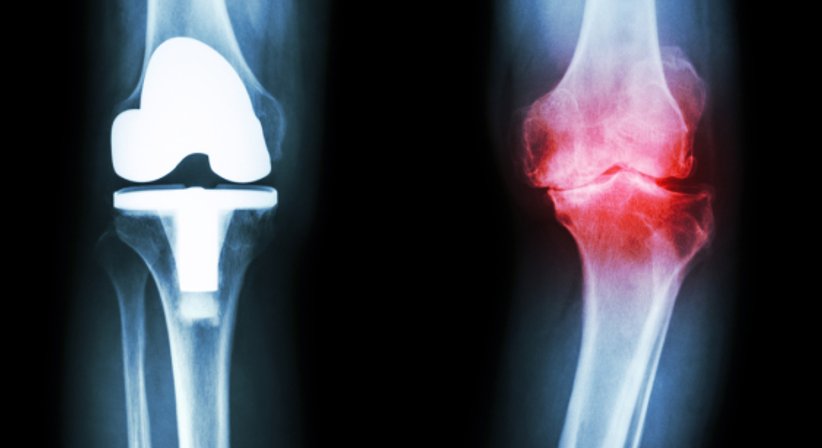

Bei Patienten mit fortgeschrittener Kniearthrose (Gonarthrose), bei welchen es trotz Ausschöpfen sämtlicher konservativer Behandlungsmöglichkeiten zu einem Fortbestehen der Beschwerden und einem Fortschreiten der degenerativen Veränderungen kommt, sollte die Implantation einer Knieprothese (künstliches Kniegelenk) unbedingt in Erwägung gezogen werden. Durch diese können die durch die Arthrose verursachten Schmerzen und Bewegungseinschränkungen langfristig beseitigt und die Lebensqualität wieder hergestellt werden.

Bei einer kompletten Knieprothese handelt es sich um den vollständigen künstlichen Ersatz des verschlissenen Gelenkknorpels. Dabei ahmt die Prothese die Form und die Funktion des körpereigenen Gelenks nach und wird exakt an die individuelle Anatomie des Patienten angepasst - denn ebenso wie kein Mensch dem anderen gleicht, unterscheidet sich auch das Kniegelenk hinsichtlich seiner Stellung, Ausrichtung und Größe voneinander. Es stehen heute viele verschiedene Prothesen in verschiedenen Größen und Formvarianten von unterschiedlichen Herstellern zur Wahl. Die Prothesengröße, die Schnittebenen und -positionen, die postoperative Beinachse und andere wichtige Faktoren werden vor der Operation genau geplant - mithilfe dieser präzisen präoperativen Planung und vorgefertigten Schnittblöcken lassen sich heute ausgezeichnete Ergebnisse (Wiederherstellung der natürlichen Beinachse, stabiles und belastbares Kniegelenk, sehr lange Lebensdauer des Implantates, Schmerzfreiheit und sehr gute Beweglichkeit) erzielen.